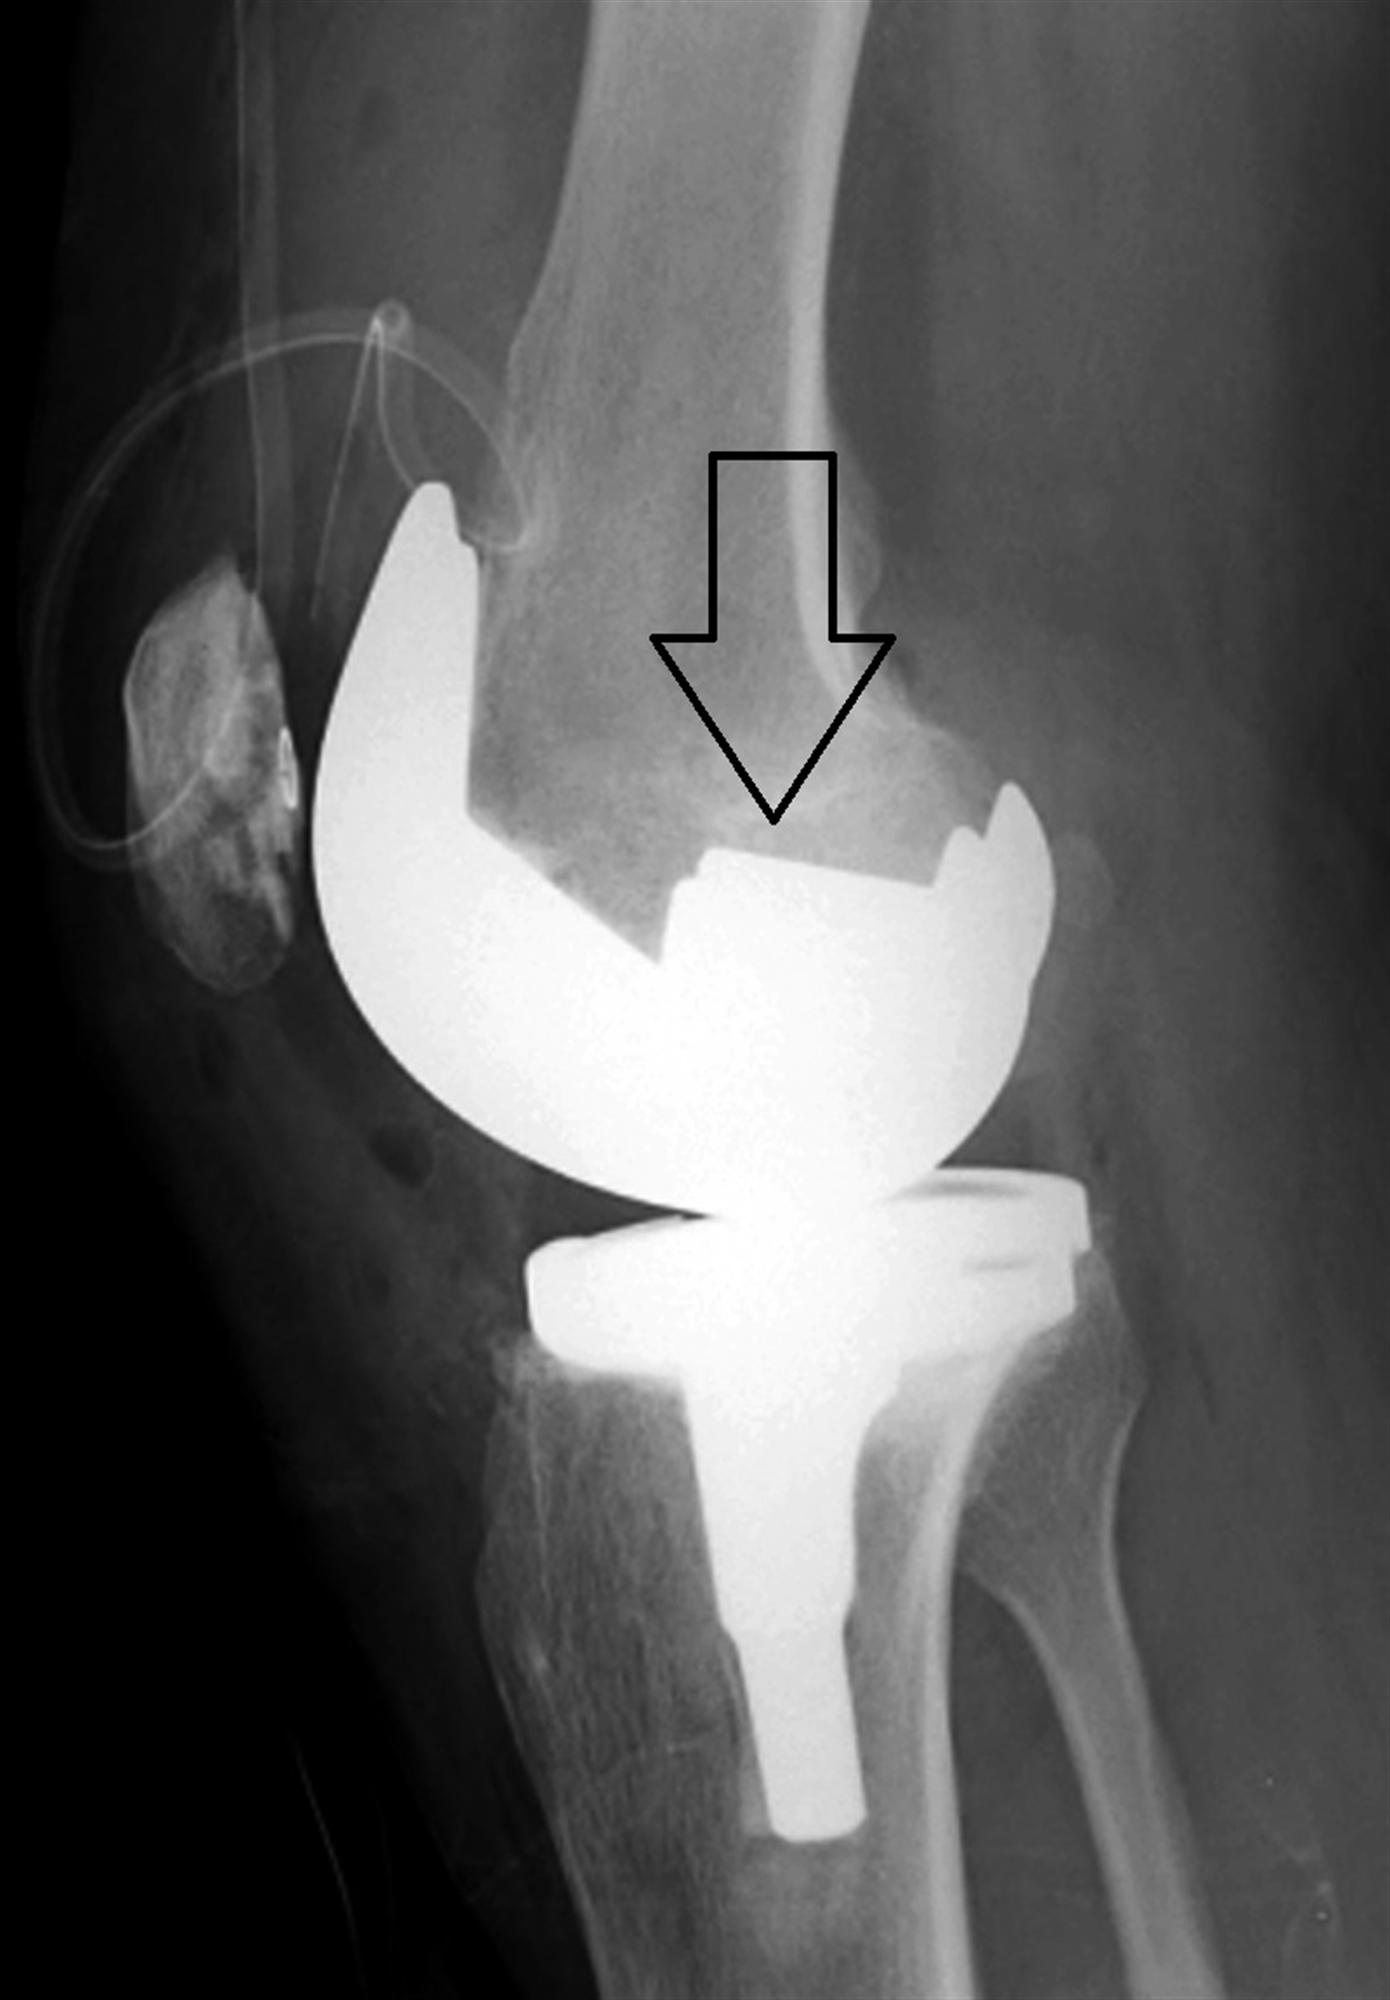

Constraint in primary total knee arthroplasty. Post Orthobullets Arthroscopic Knee Surgery Orthobullets Articular cartilage defects of the knee comprise of a spectrum of disease entities from single, focal defects to advanced degenerative disease of articular (hyaline) cartilage. This concise video guides you through the essential steps of knee arthroscopy: Arthroscopic approach to the knee. The arthroscopic approach is only recommended in minimally, or nondisplaced, fractures in young patients. Knee arthroscopy is a. Arthroscopic Knee Surgery Orthobullets.